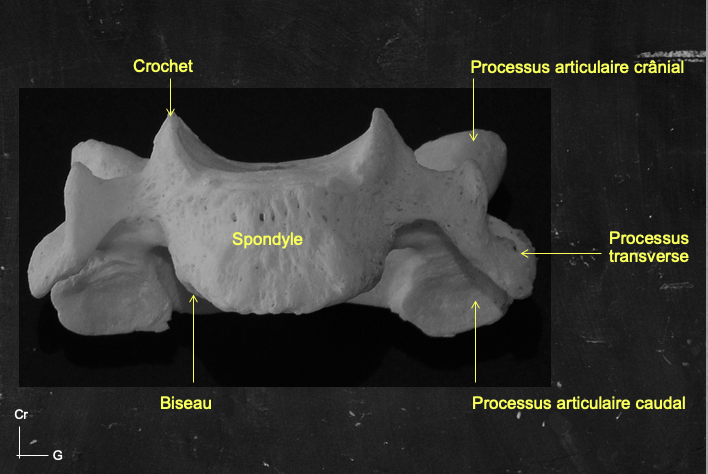

JujuG Posted May 4, 2020 Posted May 4, 2020 Bonjour, Le spondyle des vertèbres cervicales de C3 à C6 est surmonté de crochets, ainsi comme il présente une surélévation sur sa face supérieure, sa face inférieure possède un biseau concave en haut et non en bas. Quote

JujuG Posted May 4, 2020 Posted May 4, 2020 (edited) il y a 29 minutes, Paracelse a dit : mais les biseaux regardent vers l'extérieur et son plan, donc on ne peut pas dire qu'ils sont concave, et encore moins vers l'extérieur de plus, l'item semble faire référence à la forme générale du spondyle, et non à ses bords ? Le prof ne décrit pas l'orientation des biseaux en eux-mêmes, il mentionne juste leur existence à la partie infra-latérale (et super-latérale pour les crochets) Sur ce schéma on voit bien que la face inférieure est concave vers le haut. Ici le piège est fait sur la concavité en bas/en haut. Edited May 4, 2020 by JujuG Quote

Solution YoungCalvitie Posted May 4, 2020 Solution Posted May 4, 2020 @Petit_Bateau @Paracelse bonjour ! Attention, le prof fait bien la distinction lorsqu'il décrit la partie centrale du spondyle et ses bords. En effet, il y a 2 choses bien distinctes: - Au centre du corps vertébral, la surface est concave. cela vaut pour sa face supérieure et sa face inférieure. comme l'a dit @Petit_Bateau, cela permet l'accueil du DIV. - Sur la périphérie du corps, en cervical, il y a la présence d'un système crochet/biseaux sur les parties latérales des corps. Si on regarde de face, le biseau sur le pourtour de la surface inférieure donne une concavité en haut. A l'imagerie au scanner (et non radiographie), on remarque plutôt la concavité centrale des spondyles. Pour se rendre compte du système crochets/biseaux, il faudrait plutôt rechercher un scanner de face comme celui-ci Alors on se rend compte que les surfaces antéro-latérales (ou postéro-latérales c'est indifférenciable sur ce cliché) comportent une concavité vers le haut, et c'est les crochets et les biseaux situés latéralement. En espérant avoir pu aider, N'hésitez pas si besoin Quote